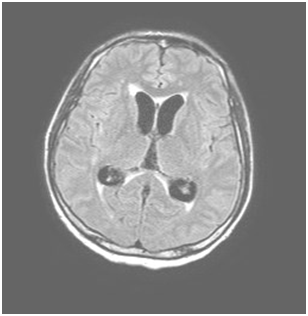

A 41 years old Filipino man who had been living in Italy for 19years and had not visited his country of origin in previous 12months for whom there was no history of comorbidity. Hospitalization in June 2016 for intermittent fever (39-40°C), which occurred in a period of approximately 15days, and a right frontal headache. No other apparent organ localizations. Upon entering the ward, the general and neurological objectivity were negative. No abnormalities were noted in any blood tests, inflammatory markers were normal, and a whole body CT was negative. Quantiferon test positive and Mantoux weakly positive, negative HIV serology. On the sixth day in hospital, 21days after the onset of fever, double vision, ptosis and anisocoria of the left eye were observed in the patient. MRI with medium contrast showed initial dilation of the supratentorial ventricular cavity (Figure 1), leptomeningeal impregnation tank prepontine, perimesencefalic, sovrasellare and silviane fissures and subtle leptomeningeal enhancement even at the level of the optic tracts and chiasm (Figure 2).

Figure 1 MRI with contrast showed dilation of the supratentorial ventricular cavity.